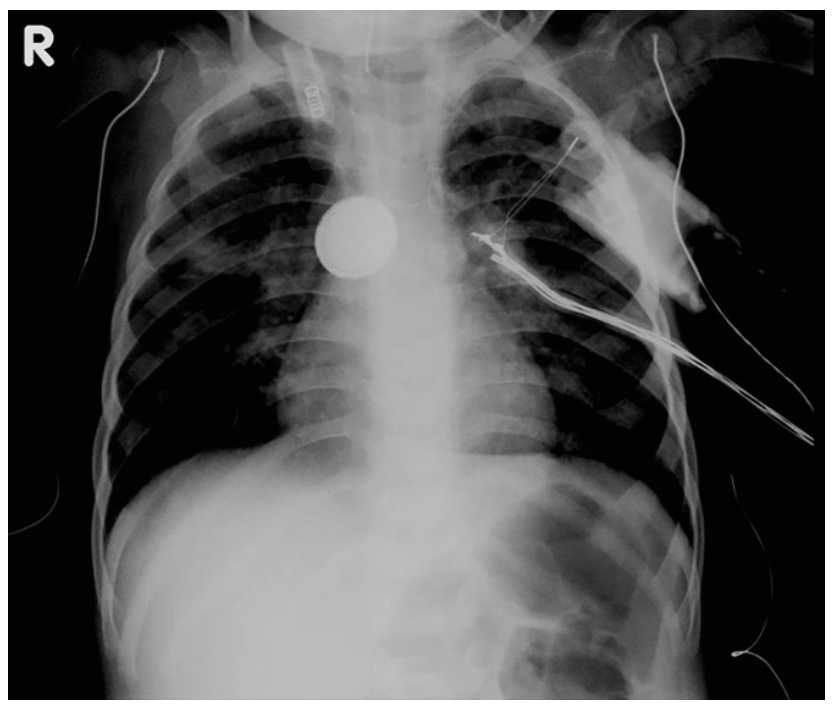

Anything that looks like blood needs to be taken particularly seriously. Brumbaugh et al showed that up to 70% of cases of fatal haemorrhage had some form of herald bleed beforehand. When you think through the fact that the presence of bleeding at all has to at least suggest that erosion has happened in the direction of a blood vessel and that the blood vessels in this region are really quite big, it definitely makes sense to be a little worried.

So in that context we turned to the polls again to ask ‘should we get this thing out quickly’ or ‘should we get that kid out (of here) quickly’ because Bara does many things but one thing it doesn’t have is the option for ECMO and that version of cardiac support. And it was a bit more split because this is tricky I guess but on balance 57% of the respondents thought maybe get that kid out.

This kid probably does need cardiac options. It may be that further imaging (say, a CT angiogram) might define what is going on a little better. It might also be that having the option for cardiology intervention with a stent to reinforce at risk areas before retrieval, plus a plan for either pre-emptively initiating cardiopulmonary bypass or peripheral ECMO could be put on the table.

What is guaranteed is a beautiful opportunity to include even more people in the team-based discussion. But to talk to more people you probably need to go somewhere with those more people.